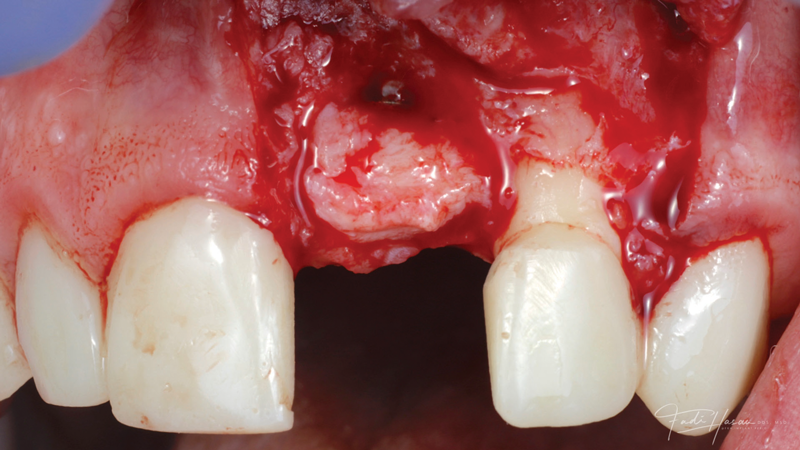

(3.) The crown was removed, and a partial thickness flap was reflected using a papilla-sparing incision design, which revealed that the implant was positioned too far facially and that its body was visible through a very thin layer of bone.

Figure 3

(4.) The crown was removed, and a partial thickness flap was reflected using a papilla-sparing incision design, which revealed that the implant was positioned too far facially and that its body was visible through a very thin layer of bone.

Figure 4